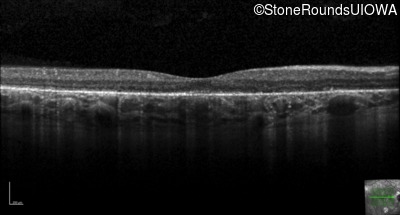

Age at visit: 33 years (Visit 2)

Age at visit: 36 years

This 31 year old woman had subtle macular abnormalities discovered incidentally earlier that year. Her medical history at the time was unremarkable except for gestational diabetes during her most recent pregnancy. Five years later she was diagnosed with type 2 diabetes managed with oral medication. Two years later she developed sufficient hearing loss that hearing aids were required. Her acuity remained 20/20 OU at that time.